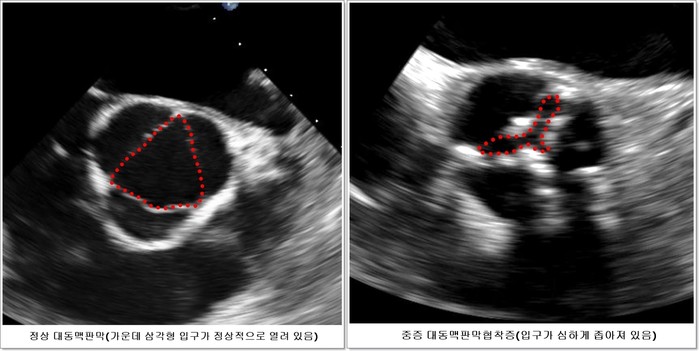

| ▲ 심장 초음파 사진(서울아산병원 제공) |

중증 대동맥판막협착증 환자의 3분의 1은 무증상으로 심장초음파 등을 통해 우연히 발견되는데, 지금까지는 심장초음파 등을 통해 무증상 대동맥판막협착증이 진단되더라도 특별한 치료 없이 주의 깊게 관찰하다가 증상이 발생하면 대동맥판막을 교체하는 수술을 받도록 권장했다. 하지만 중증이더라도 증상이 없다면 관찰을 하는 것과 증상이 없더라도 수술의 위험을 감수하고라도 수술을 하는 게 환자에게 이로운 지에 대해 명확한 기준이 없었다.

이에 강덕현 교수팀은 2010년 7월부터 2015년 4월까지 판막 입구가 0.75㎠ 이하로 좁아져 있어 중증이지만 증상이 없는 무증상 대동맥판막협착증 환자 145명 중 보존적 치료를 받은 72명과 진단 후 2개월 안에 조기 수술을 받은 73명을 추적 관찰하였다.